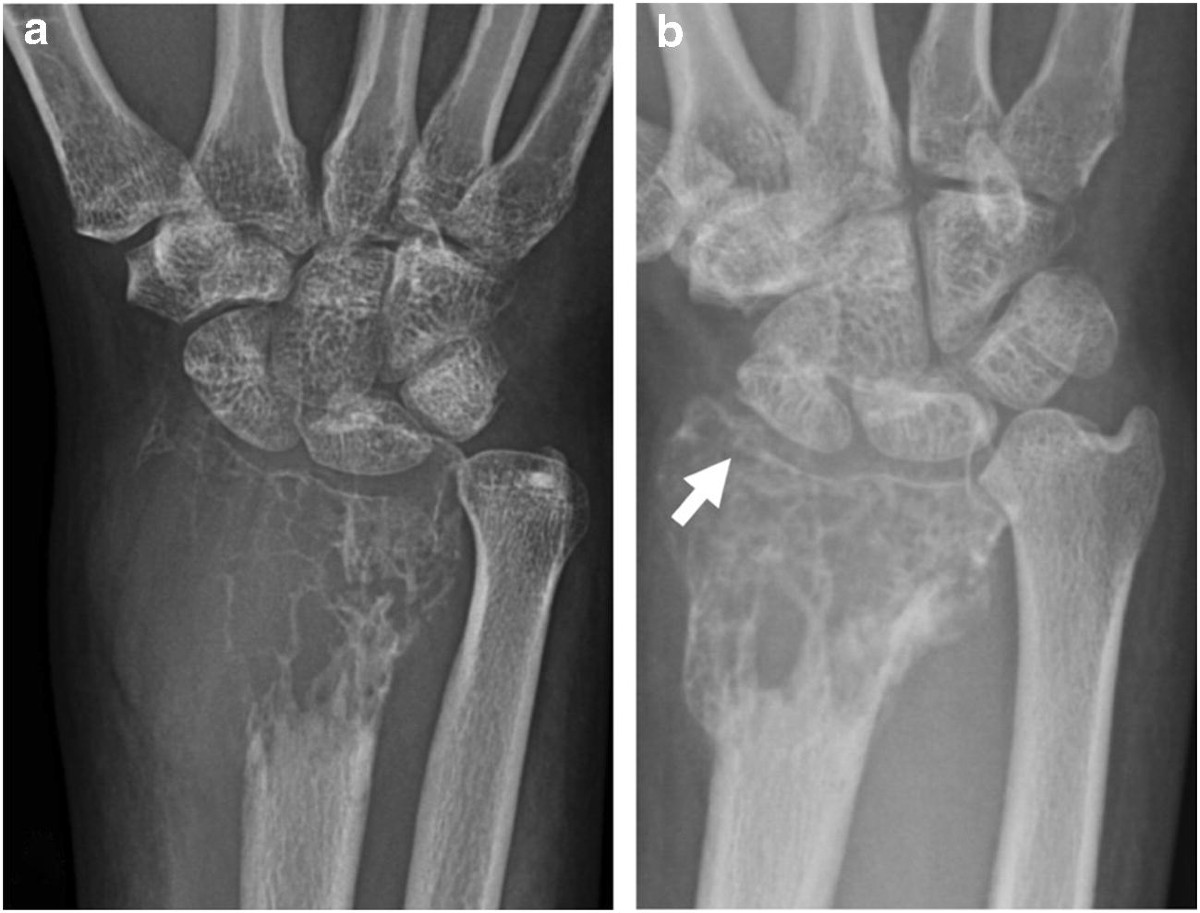

Mimics on Radiography of Giant Cell Tumor of Bone | AJR

image size: 1267x1800